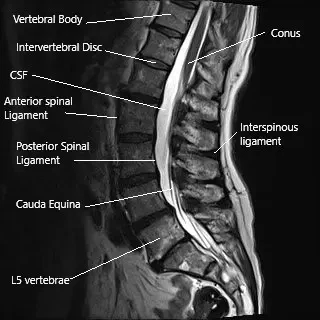

The spinal cord runs in the vertebral canal and gives numerous branches (spinal nerves) as it travels down the canal. The vertebral canal is formed by the vertebrae stacked upon each other. The lamina creates the vertebral canal’s roof, and the vertebral body forms the floor.

The spinous process is a bony projection at the back of the vertebrae. The projections may be felt under the skin as you run your hand in the lower back’s midline. The spinous processes provide stability and help in the backward movement of the spine.

MRI of the lumbar spine showing the interspinous ligament and the spinous process.